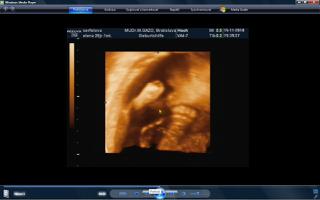

vcera som mala poradnu a teda dopadla pre mna dost prekvapujucu. mala je uz mesiac otocena dolu hlavickou a tlaci sa a tlaci. krcok sa mi zacal skracovat, ale zatial sa neotvara. a aby toho nebolo malo, tak mam aj iritabilnu maternicu. buducu nedelu idem do nemocnice na premeranie krcka a uvidi sa, co bude. aspon, ze ju uvidime 3D potvorku malu nedockavu 🙂 do mesiaca mi zrejme bude treba zaviest pesar.. tooolko radosti naraz a to som povodne vobec nemala mat poradnu, kedze som povodne dosla len s babkou na kontrolu..tak vysetrila aj mna.

caute baby. uz som tu dlho nebola. nejako nestiham. My sme uz boli na tiez na 3D a zase mala mala rucicky pred tvarickou ale daco bolo aj vidno. takze sme zistili, ze sa podoba na muza, teda aspon ten nos usta. Ma skoro 500 g takze je asi o tyzden posunuta neskor.Ak sa mi bude dat tak pridam dake fotky z toho dvd co som vybrala. Inac ja som kupovala tehotenske pancuchy v Brendone v Ba za 4 Eura. teda tenke ale mali tam aj hrubsie a tie stali 15 eur. Ja tiez rozmyslam rodit v ruzinove ale asi skor na Kramaroch. to mam blizsie domov. Ja si doplacam od marca dobrovolne nemocenske poistenie k povinnemu do maximalneho vymeriavaceho zakladu, aby som mala maximalnu matersku. Takze snad s tou materskou sa to bude dat ale horsie to bude s tym rodicovskym prispevkom.